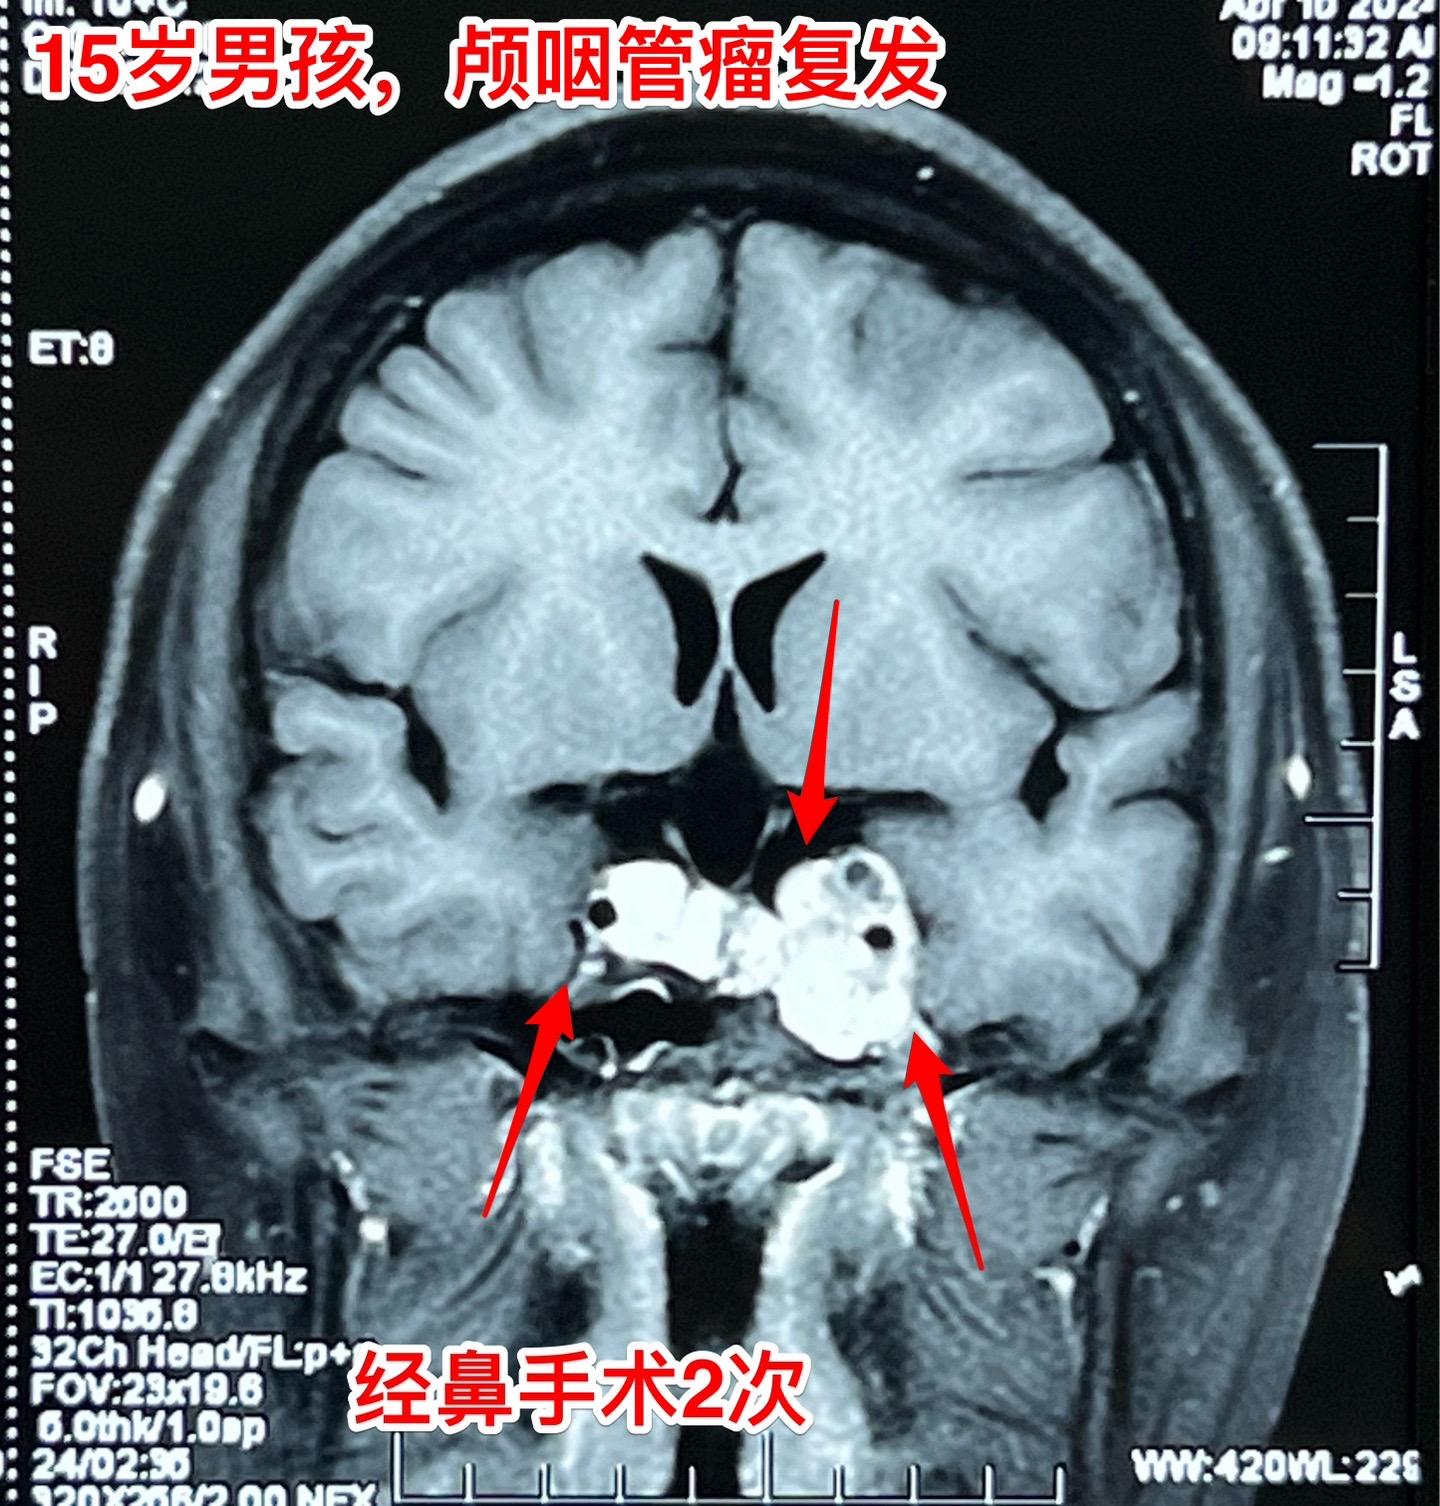

良性肿瘤也不一定容易治愈,颅咽管瘤就是。这个15岁大连市的男孩子因为颅咽管瘤先后作了两次手术,两次手术都是经鼻内镜手术。现在又复发了!从图片可以看见,这次肿瘤侵入左右两侧海绵窦,更难切除了。 在我科作了第三次手术,这次采用开颅手术。这样的手术医生很担忧出现脑脊液鼻漏的。这个病人手术后没有出现脑脊液鼻漏。 颅咽管瘤之所以容易复发是因为没有被彻底切除,如果彻底切除了也是可以治愈的。